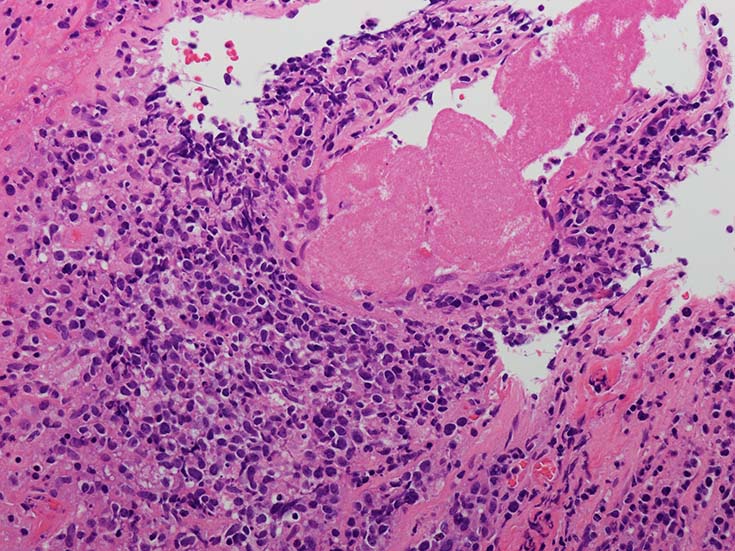

EBUS-GS(ガイドシース併用気管支腔内超音波断層法)による肺生検組織病理所見.

血管周囲性に大型類円形核や不整形核をもつ腫瘍細胞がシート状密に浸潤増殖している. Mitosisが多く認められる.細血管閉塞や破壊の所見がある.

間質にもシート状の腫瘍細胞浸潤がある. 大小 pleomorphicな傾向.(A, B). necrosisが認められる(C). 細気管支上皮直下まで密な浸潤あり, 小型リンパ球が混在している.(D)

血管中心性浸潤. 障害された血管内に血栓が形成されている.CD20陽性細胞がシート状密に浸潤, CD3陽性T細胞が多く混在している. EBER-ISH陽性 EBV感染細胞が多数認められ, >50 hpf, 定義より Grade3となる. 陽性細胞のサイズは大小さまざまであることに注意. Lymphomatoid granulomatosisの病態(WHO5thの診断では EBV-positive diffuse large B-cell lymphomaになる)をとっているが MTX-associated LPDの一型とするべき症例かもしれません.